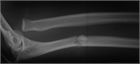

1. 尺骨骨折があった場合、橈骨頭脱臼を見流さないことがポイントである。

1. 見逃された陳旧例では前腕の回旋運動と肘の屈伸運動が障害される可能性があるため、できるだけ早く専門医に紹介する。